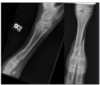

Une génisse angus de grande valeur génétique est présentée avec une boiterie de non appui du membre postérieur gauche avec enflure. Difficultés à se lever et beaucoup d’enflure dans la région. Voici la radiographie, lequel est vrai : a) Le clou verrouillé est une méthode d’immobilisation à éviter dans ce cas b) Fixateur externe de type 2 est facile à implanter permettant une grande liberté de mouvement c) Ce veau est particulièrement susceptible de développer des maladies néonatales d) Les tiges intramédullaires sont le traitement de choix avec excellent pronostic e) La béquille de thomas est la méthode de choix pour immobiliser cette fracture

**c) Ce veau est particulièrement susceptible de développer des maladies néonatales** ## Footnote => Parce qu’ils ont de la difficulté à se lever et à se tenir debout,l’ingestion de colostrum est souvent insuffisante. =>ttt= Administration de plasma ou de sang entier si absence d’immunité passive. **=Tiges intramédullaires insérées de façon rétrograde = Clou intramédullaire**